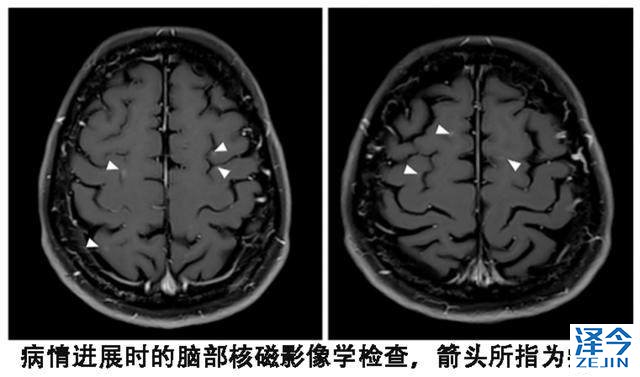

2015年9月,患者进行了视力检查发现双影,根据影像学检查、腰椎穿刺获得脑脊液的细胞学检查,确定脑部病灶进展且出现了脑膜转移。

由于特罗凯入脑效果本身还可以,患者因此使用每周一次的特罗凯脉冲治疗,但是情况并不乐观,很快骨、肺部、脑部病灶出现了进展。患者的视觉双影依然存在,脑脊液细胞学检查显示有癌细胞。血液基因检测T790M突变是阴性的,这个时候是否值得换用第三代靶向药物泰瑞沙呢?

患者尽管血液基因检测T790M阴性,但是依然换用了第三代靶向药物泰瑞沙(AZD9291),每天的剂量为80毫克,结果出现了奇迹。患者的视觉双影没有了,脑脊液的细胞学检查也为阴性,脑部核磁显示脑皮质损伤有所改善。